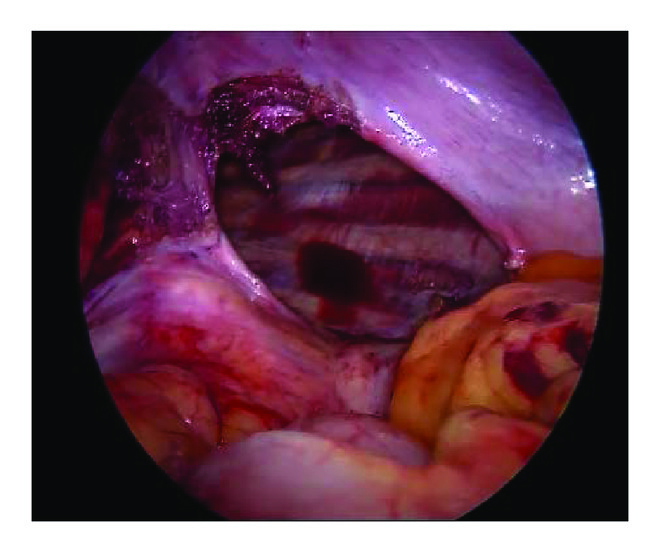

With a preoperative diagnosis of diaphragmatic hernia, the laparoscopic repair was planned. The patient was placed in 30° reverse trendelenburg position with a sand bag under left lower chest. After insufflations of abdomen, five ports were placed. Presence of diaphragmatic hernia (Table 3) was confirmed, and 4 cases of Bochdalek hernia (BH), 8 cases of left eventration of diaphragm, and one case of right-sided eventration of the diaphragm were included in this study. Largest defect found on the left side was 15 × 6 cm (Figure 1) and on the right side it was 15 × 8 cm. Stomach, small intestine, transverse colon, and omentum were found to be in the hernial sac on left side.

The contents were reduced with the help of harmonic scalpel dissection and however thin sacs were excised. After reduction of contents, hernial orifice was repaired with Polypropylene—1/0 (Ethibond/Prolene). Interrupted horizontal mattress sutures were placed buttressed by Teflon pieces. A 20 × 15 cm (Figure 2) composite mesh (Parietex) was placed over the defect fixed with nonabsorbable tackers. Diaphragmatic plication with (Ethibond) mesh placement was a procedure done in all 9 cases of eventration of the diaphragm.